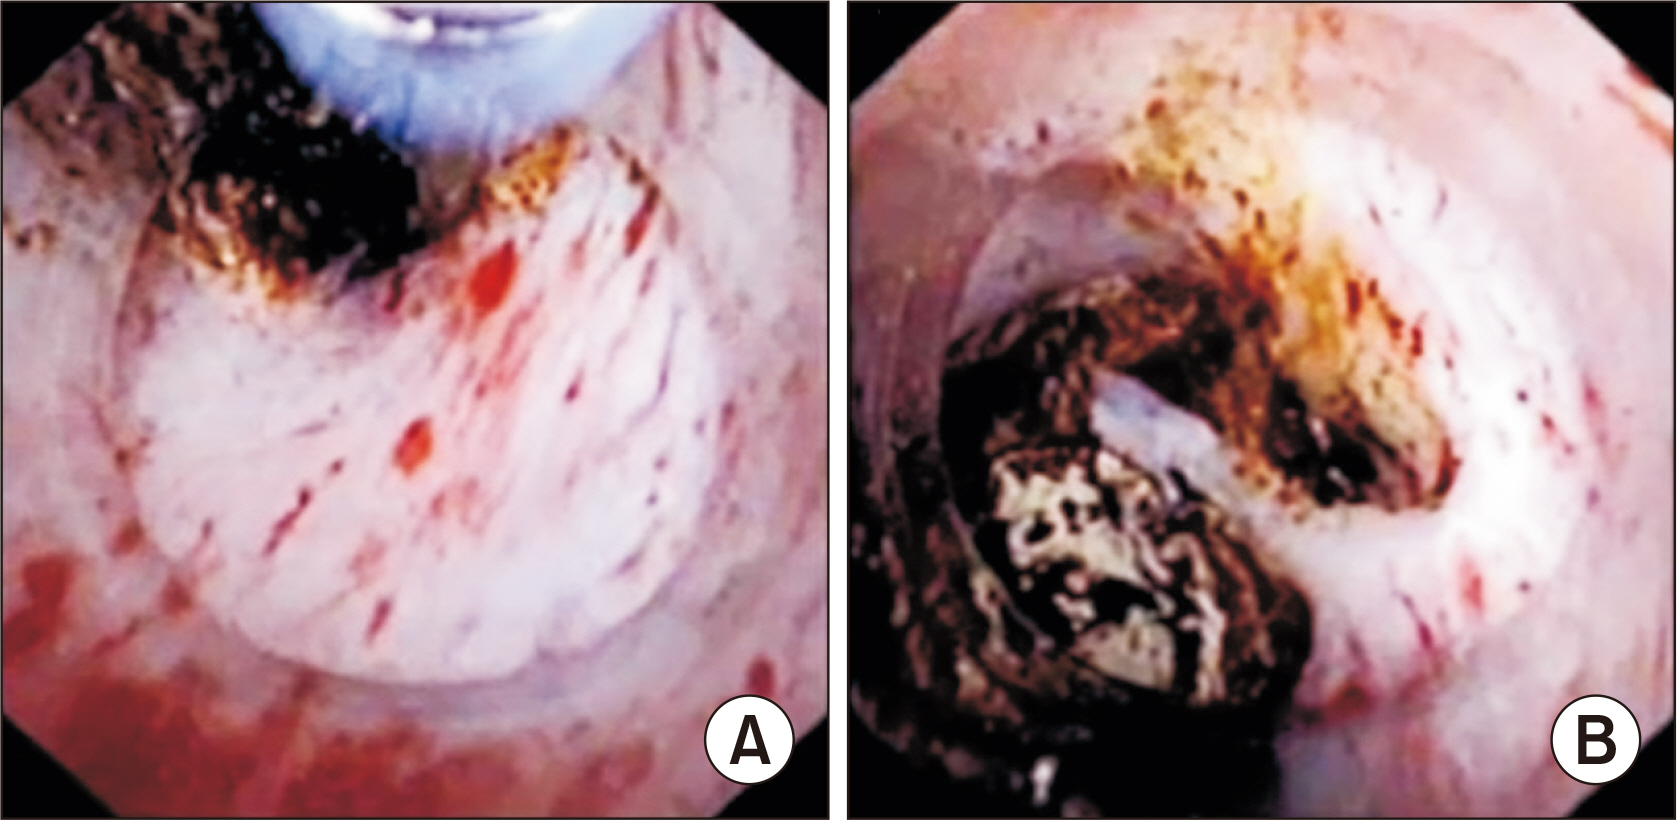

- Laparoscopic subtotal cholecystectomy (LSC) has been a safe and viable alternative to conversion to laparotomy in cases of severe cholecystitis. The objective of this study is to determine the utility of intraoperative choledochoscopy in LSC for the exploration of the gallbladder, cyst duct, and subsequent stone clearance of the cystic duct in cases of severe cholecystitis. A total of 72 patients diagnosed with severe cholecystitis received choledochoscopy-assisted laparoscopic subtotal cholecystectomy (CALSC). A choledochoscopy was performed to explore the gallbladder cavity and/or cystic duct, and to extract stones using a range of techniques. The clinical records, including the operative records and outcomes, were subjected to analysis. No LSC was converted to open surgery, and no bile duct or vascular injuries were sustained. All stones within the cystic duct were removed by a combination of techniques, including high-frequency needle knife electrotomy, basket, and electrohydraulic lithotripsy. A follow-up examination revealed the absence of residual bile duct stones, with the exception of one common bile duct stone, which was extracted via endoscopic retrograde cholangiopancreatography. In certain special cases, CALSC may prove to be an efficacious treatment for the management of severe cholecystitis. This technique allows for optimal comprehension of the situation within the gallbladder cavity and cystic duct, facilitating the removal of stones from the cystic duct and reducing the residue of the non-functional gallbladder remnant.

Figure